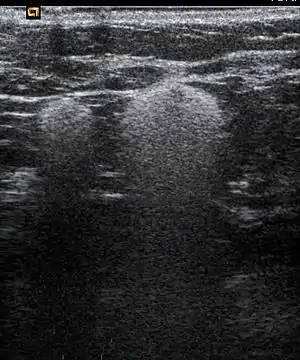

Snowball like hyperechogenic axillary lymph nodes in a woman with silicone implants removed due to complications